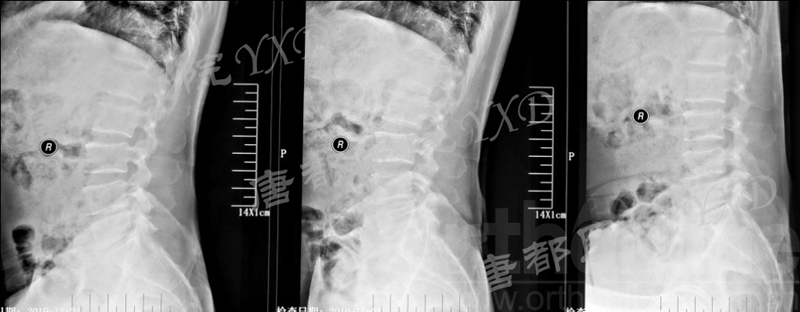

影像学检查:

诊断:腰椎间盘突出症术后复发

手术方案:显微镜辅助MI-TLIF腰椎翻修术